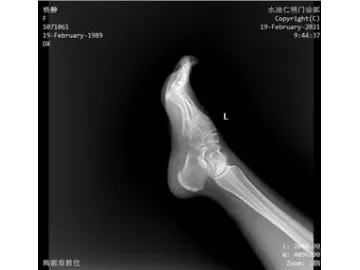

El modelo SHO-CMX01 es un sistema de rayos X fijado al techo pensado para quienes buscan precisión, rapidez y calidad en sus exámenes de imagen. Ideal para estudios de tórax, columna, abdomen y extremidades, se adapta perfectamente a centros médicos, departamentos de radiología, unidades de ortopedia y diagnóstico, entre otros. Este dispositivo médico no solo cubre radiografías convencionales, sino que también está preparado para procedimientos más exigentes como uniones de imágenes, visualización detallada de fracturas o estudios integrales en reconocimientos médicos. Es una solución integral que responde a las demandas clínicas más exigentes.Está equipado con un generador de 65.5 kW, un tubo de rayos X Canon de muy buen rendimiento, y dos detectores de panel plano (uno con cable y otro inalámbrico) que garantizan imágenes nítidas. Además, su colimador motorizado le permite ajustar el campo de exposición de forma rápida y precisa, optimizando cada procedimiento.

- Este sistema integra dos detectores planos (FPD), compatibles tanto con conexión por cable como inalámbrica, para adaptarse a distintas necesidades clínicas.

- Gracias a su formato de 17" x 17", ofrece un campo de visión amplio que evita tener que mover el detector durante el examen, facilitando así una visualización continua y sin interrupciones.

- Su tecnología de vanguardia garantiza imágenes nítidas, sin distorsiones y con una resolución excepcional, lo que mejora notablemente la precisión diagnóstica.

- Permite capturar imágenes puntuales en milisegundos durante la visualización o reproducción de los estudios. Esto brinda a los profesionales la posibilidad de detectar áreas sospechosas con mayor certeza, reducir errores de diagnóstico y acelerar la elaboración de informes.